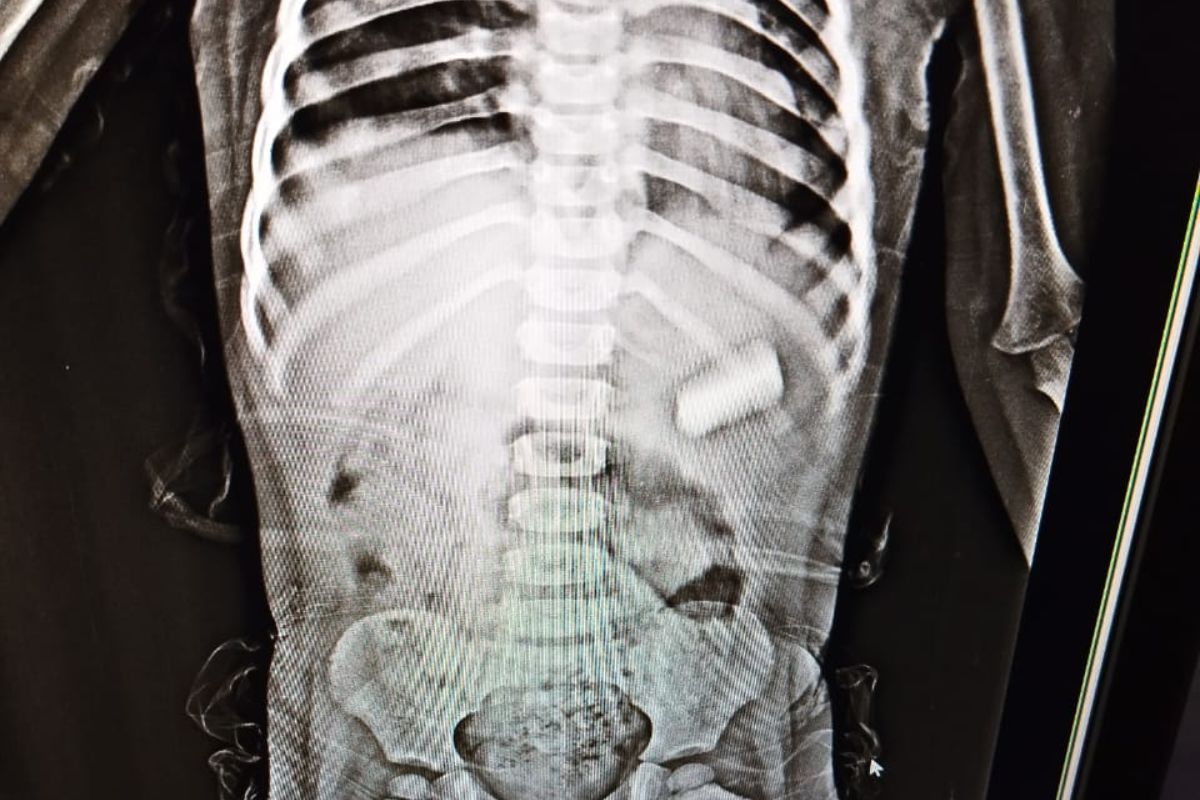

पटना सिटी के एक परिवार की सांसें उस समय अटक गईं, जब 3 साल की मासूम बच्ची ने स्पोर्ट्स-स्पोर्ट्स में पेंसिल बैटरी निगल ली. परिजनों ने पहले केला खिलाने जैसे कई घरेलू नुस्खे अपनाने की कोशिश की, पर कोई फायदा नहीं हुआ. बच्ची की हालत बिगड़ती देख परिजन उसे तुरंत सत्यदेव सुपर स्पेशियलिटी हॉस्पिटल लेकर पहुंचे.

अस्पताल में आपातकालीन स्थिति में डॉक्टरों की टीम ने तुरंत उसका इलाज शुरू कर दिया. वरिष्ठ यूरोलॉजिस्ट और हॉस्पिटल के डायरेक्टर ने बताया की डॉक्टरों की टीम ने दूरबीन (एंडोस्कोपी) तकनीक के माध्यम से बैटरी को सफलतापूर्वक बाहर निकाला. बच्ची को एक दिन ऑब्जर्वेशन में रखा गया और अब वह पूरी तरह स्वस्थ होकर घर लौट चुकी है.

इस पूरे मामले को लेकर डॉ. अमृता ने बताया कि “बच्ची महज तीन साल की थी, जिसके कारण यह प्रक्रिया काफी चुनौतीपूर्ण थी. अगर बैटरी पेट में रह जाती, तो उससे निकलने वाला जहरीला पदार्थ पूरे पेट में फैल सकता था, जो जानलेवा साबित होता.” उन्होंने बताया कि इतनी कम उम्र में एनेस्थीसिया देना भी एक जोखिमपूर्ण कदम था, लेकिन टीम ने सावधानी से सफल ऑपरेशन किया.